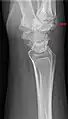

Additional images

Carpal boss in plain X-Ray.